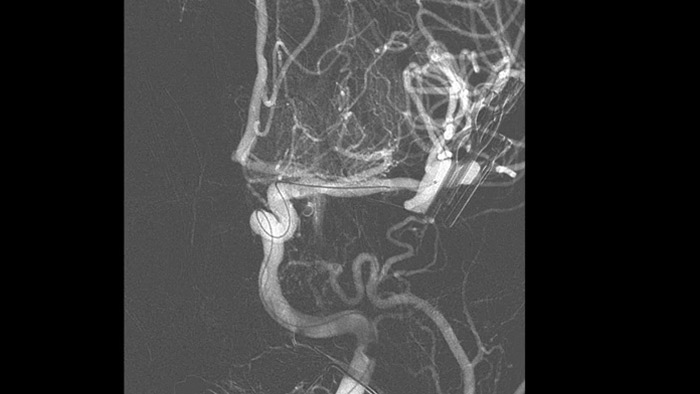

Технология ClarityIQ снижает дозу облучения на 75% при проведении DSA* для пациентов с неврологическими особенностями, создавая при этом изображения, качество которых не отличается от качества изображений системы без ClarityIQ, что является важным преимуществом при лечении большого числа пациентов. Технология автоматической компенсации артефактов движения ClarityIQ незаменима при установке устройств маленького размера в основании черепа, т. к. она подавляет артефакты черепа и движения.

Технология ClarityIQ снижает дозу облучения на 75% при проведении неврологических исследований в режиме DSA1, создавая при этом изображения, качество которых не отличается от качества изображений системы без ClarityIQ. Технология автоматической компенсации артефактов движения предоставляет ключевое преимущество при проведении процедур установки устройств маленького размера на сосуды головного мозга, т. к. стабилизирует перемещения черепной коробки и подавляет артефакты движения.